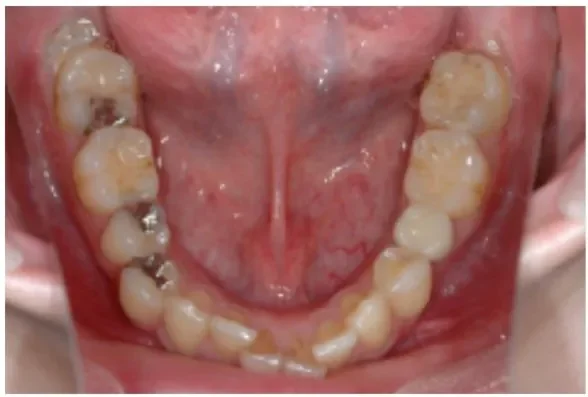

Before

After

虫歯によって欠損してしまった箇所へのインプラント治療

5ヶ月、8回 / 420,000円リスク・副作用:インプラント粘膜炎およびインプラント周囲炎